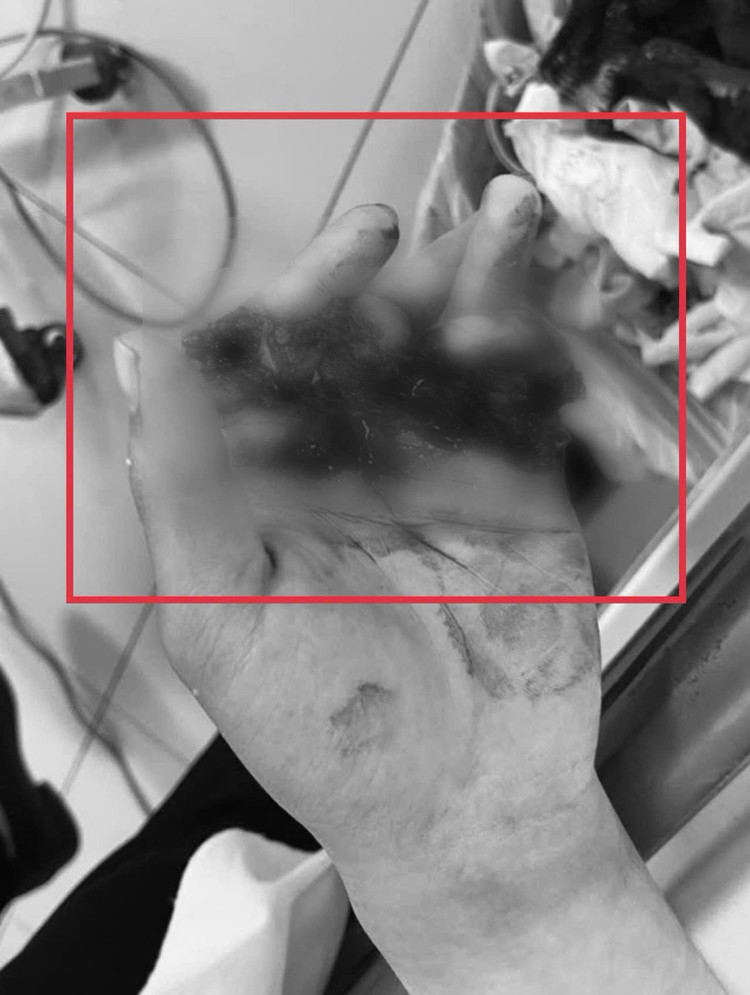

Tổn thương bàn tay - Ảnh BVCC

Một phút sơ suất trước chiếc máy dập tôn công nghiệp đã khiến anh N.V.H (25 tuổi ở Hà Nội) suýt mất vĩnh viễn chức năng bàn tay. Lưỡi dập thủy lực rộng hơn 1 cm rơi xuống, nghiền nát cùng lúc bốn ngón tay – biến chúng gần như “đứt rời” chỉ còn dính lại bằng một cầu da rất mỏng.

Khi được đưa tới Bệnh viện Bệnh Nhiệt đới Trung ương, các ngón tay đều trắng bệch, lạnh, xẹp, hoàn toàn mất tưới máu – tình trạng vô cùng nguy kịch.